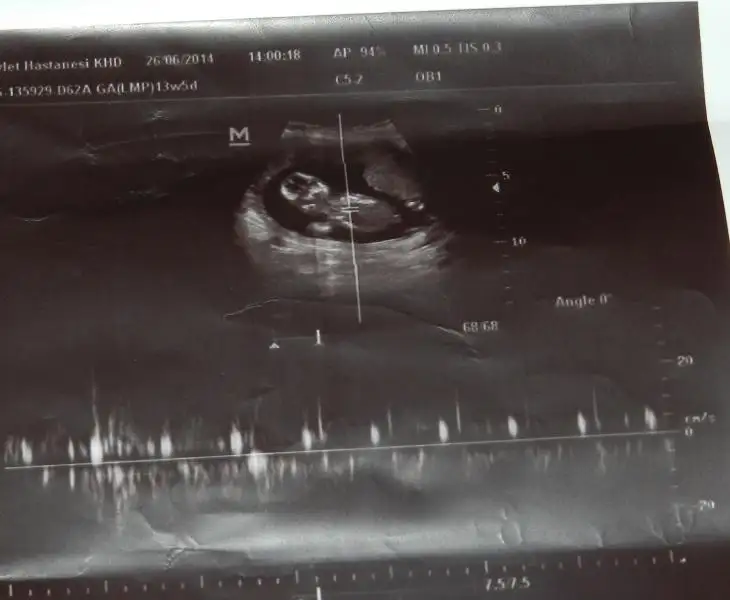

Benim 4 boyutlu değil ama bakabilirmisiniz nubuna. Şu an 13+0 Daha 10 gün var kontrole. Ilkinde 11 hafta 5 gün,ikincisinde 12 hafta 3 günlüktük.

$ImageUploadedByKadınlar Kulübü1403871661.181270.webp